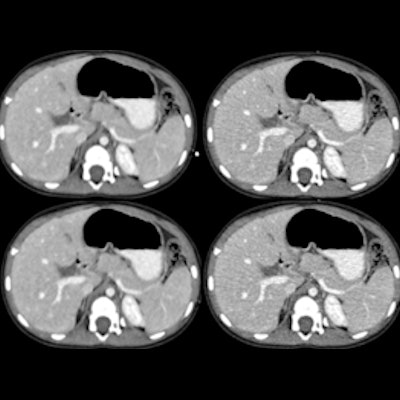

In a second Sunday afternoon presentation, Italian researchers looked at whether CT's performance varied depending on the prevalence of COVID-19 disease in a region.

A group led by Dr. Marcello Petrini of Guglielmo da Saliceto Hospital in Piacenza, Italy, assessed the modality's diagnostic performance for severe illness by comparing an outbreak phase to an ensuing period of lower disease incidence (first outbreak, high prevalence: February 21 to March 7; second period, lower prevalence after 28 days of lockdown: April 6-13).

The researchers used RT-PCR results as the reference standard to evaluate CT's sensitivity, specificity, positive predictive value, and negative predictive value.

The high-prevalence group included 198 patients and the low-prevalence group included 146 patients. The team found that while CT had about the same sensitivity regardless of disease prevalence, specificity was lower during the time of higher disease prevalence:

The study's main finding of a high PPV rate on chest CT during the early-outbreak, high-prevalence period in Italy and a high NPV rate during the second, low-disease-prevalence period should help clinicians more effectively manage patients suspected of COVID-19, Petrini concluded.

"Even with a negative CT, the likelihood to have COVID-19 pneumonia is still high during the high-prevalence phase of the disease while it is very low in the low-prevalence period," he said.